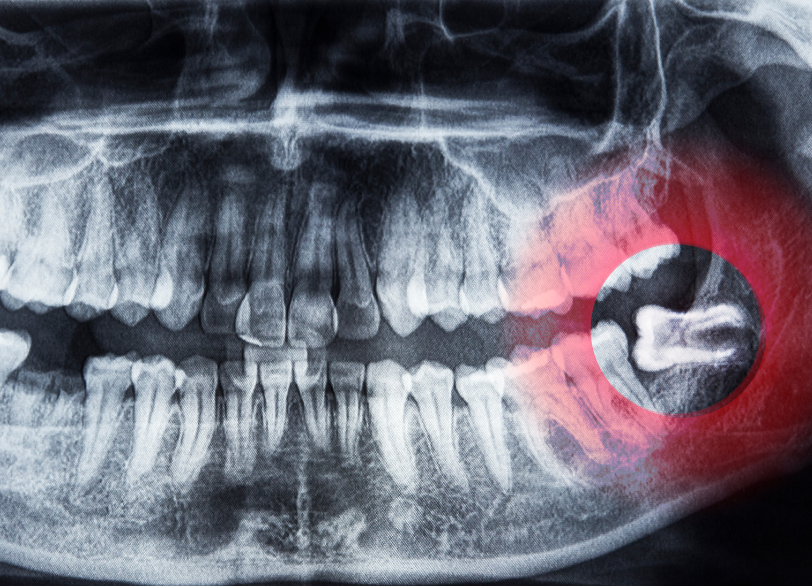

親知らずとは、一番奥に生えてくる永久歯のことで正式には「第三大臼歯」と呼ばれます。

奥歯の「6歳臼歯(第一大臼歯)」「12歳臼歯(第二大臼歯)」の、さらに奥に生えてきます。

一般的に18歳から20歳頃に生え始めることが多いですが、生えてくる時期や生え方には個人差が非常に大きいです。

現代人は食生活の変化などから顎の骨が小さくなる傾向があり、親知らずが最後に生えるための十分なスペースがないケースが増えています。

そのため、様々なトラブルを引き起こす原因となりやすいのです。

親知らずが斜めや横向きに生えたり、歯茎が一部かぶったままだったりすると歯と歯茎の間に深い溝ができます。この溝は歯ブラシが届きにくく、細菌が溜まりやすいため炎症を起こしやすい状態です。

体調を崩して免疫力が落ちた時などにこの細菌が増殖し、歯茎が赤く腫れたり、強い痛みが出たり、膿が出たりします。これが智歯周囲炎です。

親知らずが横向きに生えてくると、手前の大切な歯(第二大臼歯)の根元を強く押し続け歯の根を溶かしてしまう(吸収)ことがあります。

また、親知らずと手前の歯の間には非常に虫歯になりやすい「死角」ができます。

ご自身では気づかないうちに、手前の歯が大きな虫歯になってしまうケースも少なくありません。

2. 歯科用CTによる「三次元」の精密診断

口腔外科手術の安全性を支える上で、今や「歯科用CT」は欠かすことのできない設備です。

特に下顎の親知らずの抜歯において、最も注意すべきなのは顎の骨の中を通る太い神経(下歯槽神経)や血管との位置関係です。

従来の二次元レントゲンでは、歯の根と神経が重なって写っているようにしか見えずその正確な距離や前後関係は「推測」するしかありませんでした。

当院では、歯科用CTを導入し骨の中の状態を「三次元の立体画像」で再構築します。これにより、以下のことが手術前に「目で見える」状態で把握できます。

- 歯の根の正確な形や湾曲の度合い

- 神経や血管との、ミクロン単位での正確な位置関係(距離)

- 骨の中に隠れた病巣(嚢胞など)の正確な広がり

このCTによる精密診断が、神経の麻痺などを防ぎ手術の安全性を飛躍的に高めるのです。